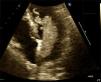

After the procedure, the patient was transferred to the coronary care unit. Cardiac troponin I (cTnI) and creatine kinase-MB (CK-MB) were measured. Peak cTnI was 210 ng/ml (reference value <0.01 ng/ml), and peak CK-MB was 415 ng/ml (reference <7.7 ng/ml). The following morning transthoracic echocardiography was performed, which revealed lateral wall and apical akinesia with ejection fraction (EF) of 40-45% and a large left atrial mass. The mass (a myxoma) in the left atrium was attached to the atrial septum and appeared pedunculated, villous and highly mobile, measuring 2.5 cm wide and 6.7 cm long (Figure 4). A full neurological examination was normal and a computed tomography scan of the brain showed no acute abnormalities. Five days later, the patient underwent open heart surgery to remove the left atrial mass. Its pathology was compatible with a villous myxoma. Echocardiography was repeated pre-discharge and showed an EF of 55%. There were no complications and the patient was discharged home.

Figure 4.

Echocardiogram showing a villous left atrial myxoma prolapsing into the left ventricle in the diastolic phase.